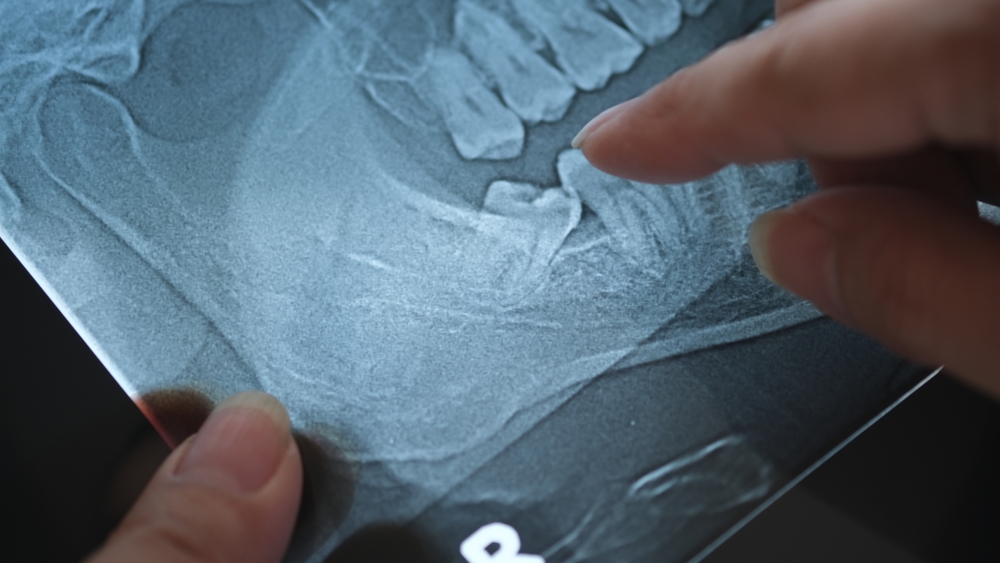

Molars, especially wisdom teeth, are often considered the most painful teeth to have removed. These teeth are larger and deeply rooted in the jawbone, which can make their extraction more invasive and thus more painful. Impacted wisdom teeth, meaning those trapped under the gum or growing at an angle, often require surgical intervention, further increasing post-procedure discomfort, as the gums and jawbone around these teeth may experience swelling and soreness for several days.

The level of pain varies depending on the type of tooth removed and the complexity of the extraction. Simple extractions, such as removing a loose front tooth, tend to cause minimal discomfort, while removing molars or impacted wisdom teeth can result in more significant soreness, due to larger teeth often having deeper roots and potentially requiring more invasive techniques, such as cutting into the gum or bone to remove the tooth.